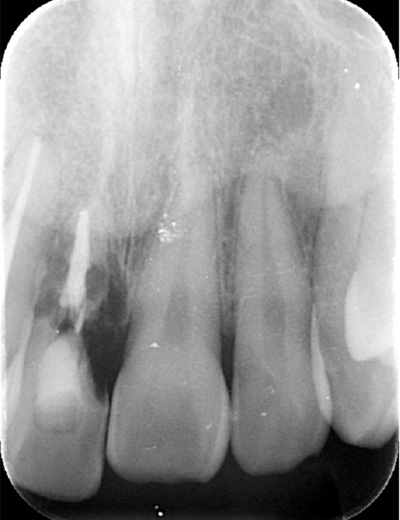

| 年代・性別 | 30代 男性 |

|---|---|

| 主訴 | 前歯が腫れた |

| 治療期間 | 約18ヶ月 |

| 費用 | 700,000円 |

| 治療内容 | インプラント、部分矯正、骨造成、結合組織移植、セラミック修復 |

| 治療に伴うリスク | インプラント周囲炎 セラミックの破折、脱離 |